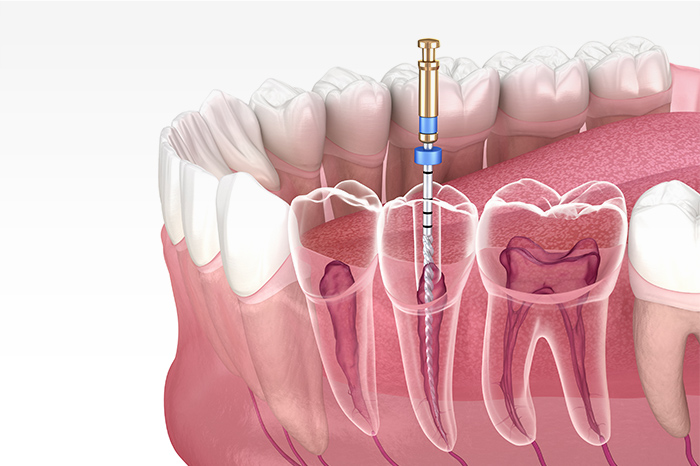

根管治療とは、むし歯が神経まで達した際に歯の根の中をきれいにする治療です。むし歯が進行すると強い痛みや膿がでてくる症状があります。その際に細菌などに感染した神経や血管を取り除き、歯を抜かずに残すことを目的として治療します。歯の強い痛みや腫れなどにお困りの場合は、愛知県岡崎市美合町・美合駅前にある当院へご相談ください。

当院では、精密な検査と先端技術を活用して検査を行います。歯科用CTで根管状態を詳細に確認し、感染症を軽減できるラバーダムを使用し、マイクロスコープで患部を拡大しながら治療を行います。感染した組織を取り除く際は、NiTiファイルを用いて根管内部まで徹底的に清浄します。当院では患者さんの負担を軽減させるために、診察から治療まで先端設備を使用し全力で治療を行います。

ニッケルチタンファイル

ニッケルとチタンの合金で作られた歯科治療器具で、手動で使用するタイプと、ロータリーエンジンに装着して使用するタイプの2つがあります。

根管拡大装置